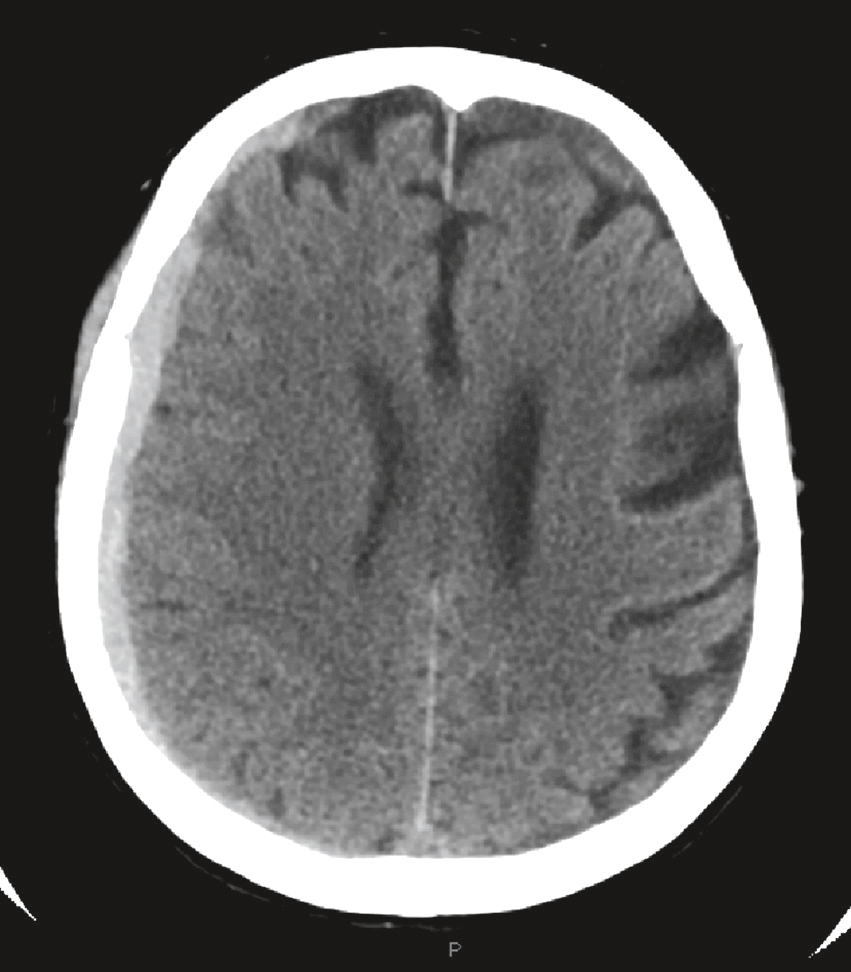

QRM 28

Une patiente de 84 ans présente des céphalées inhabituelles depuis 10 jours. L’imagerie suivante est réalisée (fig. 32.2). À propos de cette imagerie, quelle(s) est (sont) la (les) proposition(s) exacte(s) ?

Cette coupe axiale, faite avec un scanner cérébral sans injection, montre des concentrations faibles diffuses de l'hémisphère cérébral gauche avec une perte de différenciation des substances de matière grise et blanche et d'élimination du sulcus cortical. Ces signes sont typiques de l'origine de l'ischémie aiguë de l'œdème cérébral. L'aspect mondial provoque un infarctus d'expansion des territoires territoriaux intérieurs gauche. L'absence de saignements visibles et d'uniformité de faibles concentrations augmente l'hypothèse d'un grand accident vasculaire cérébral ischémique. La ligne centrale reste le centre du monde, indiquant les premiers niveaux d'urgence, mais nécessite la gestion des urgences pour éviter la dégradation secondaire.

- A IRM cérébrale montrant une atrophie corticale gauche

- B scanner cérébral injecté montrant une prise de contraste arachnoïdienne

- C hémorragie cérébrale

- D hématome sous-dural aigu

- E hématome extradural